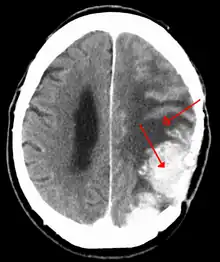

![]() | |

| A contrast-enhanced CT scan of the brain, demonstrating the appearance of a meningioma | |

Meningiomas are visualized readily with contrast CT, MRI with gadolinium,[22] and arteriography, all attributed to the fact that meningiomas are extra-axial and vascularized. CSF protein levels are usually found to be elevated when lumbar puncture is used to obtain spinal fluid. On T1-weighted contrast-enhanced MRI, they may show a typical dural tail sign absent in some rare forms of meningiomas.[17]